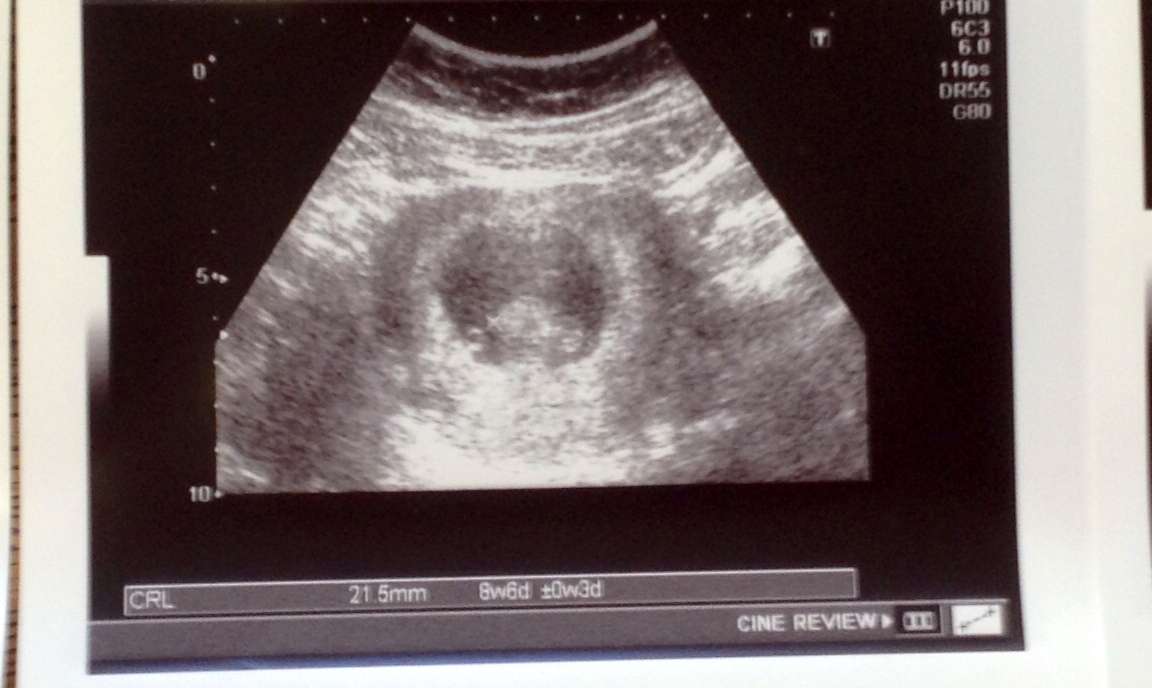

I think I god the shittiest ultrasound as far as clarity goes (and this was the best one! All the others are pretty much all black). To me the sac looks completely vertical with baby at the bottom. So I don't think the Ramzi prediction is going to work for me

Mine is super hard to see, but what do you guys think? It was abdominal and the baby measured 8+6. Is that too late for this "theory"? I will get my blood test results in the next few weeks and am curious about whether they will align.